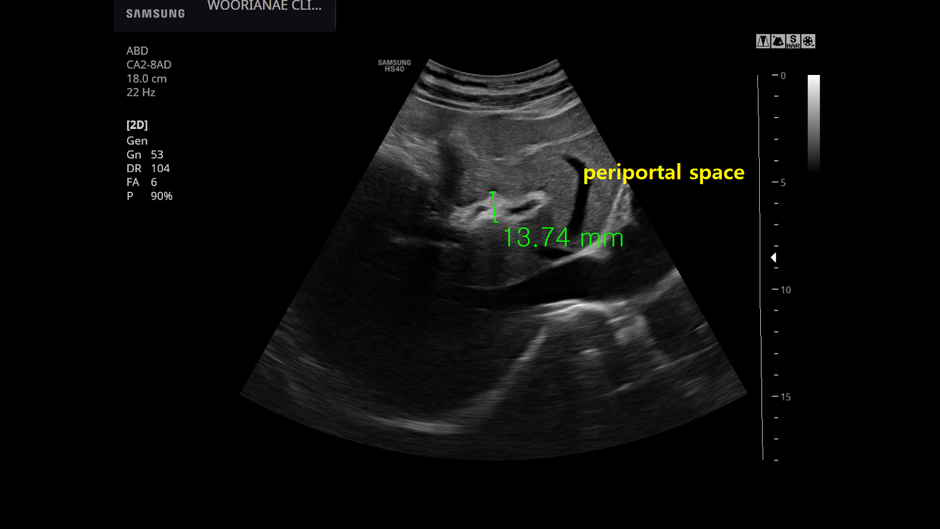

50대 중반 남자 21년 진료 당시 언급이 없었으나... 간암 검진 등 검진 예약하고 방문 ; 과거력을 다시 확인하니 약 10여년전 인터페론으로 C형 간염 완치 (완치 확률은 30%였던 과거 치료) periportal space에 간격이...